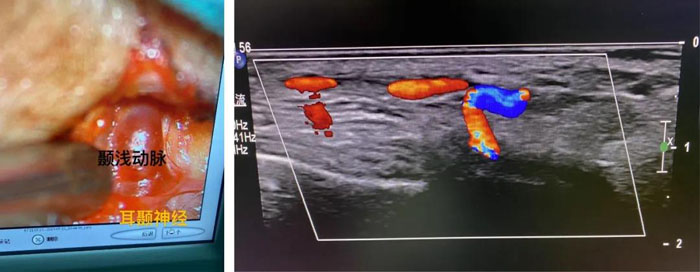

患者女,65歲,雙側顳部及枕部持續搏動性跳痛30余年,就診我院頭面痛門診。郝懷勇主治醫師經過細致的體格檢查,發現引起她頭痛的根源是顳部的耳顳神經和枕部的枕大神經。借助術中超聲,在李永濤主任醫師指導下,郝懷勇主治醫師在顯微鏡下為患者行“耳顳神經及枕神經微血管減壓術”。術中發現神經與周邊纖維筋膜組織黏連緊密,顯微鏡下松解神經被卡壓部位,并處理纏繞神經的血管。術后疼痛消失,門診隨訪無復發。